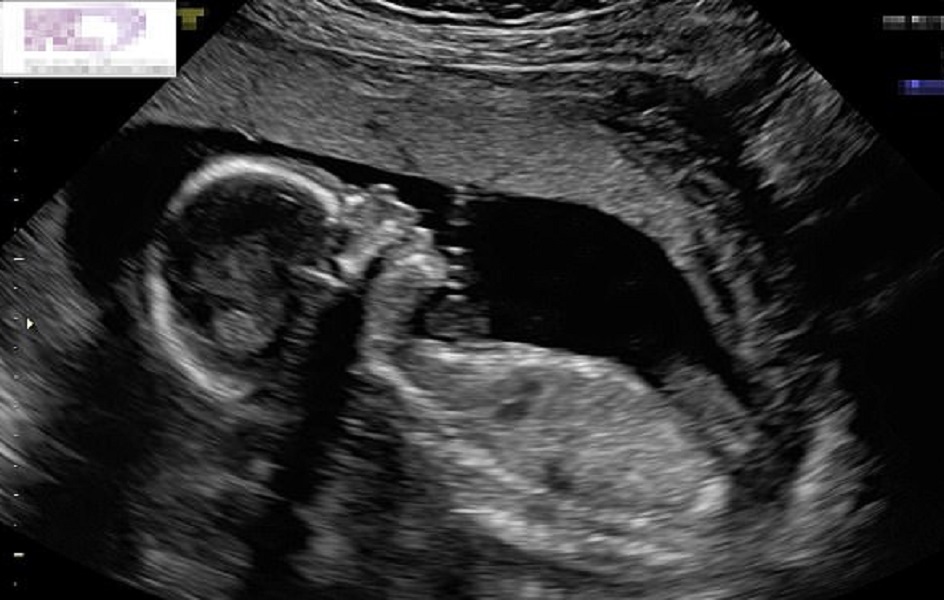

NEW YORK – Una coppia di genitori in attesa del loro secondo figlio sono rimasti sorpresi quando hanno visto la scansione della radiografia fatta alla mamma, alla ventesima settimana di parto. All’interno del grembo materno, il piccolo nato sembra dare loro il “cinque”. Libby e Mathew Vlasic di New York sono rimasti colpiti e soprattutto felicissimi di sapere che Miles, il loro figlio di sei anni, avrà una sorellina che sta crescendo proprio bene. Lo dimostra anche la foto che i genitori hanno deciso di condividere facendola diventare virale in poco tempo.

La scansione è stata fatta alla ventesima settimana. La coppia è rimasta favorevolmente sorpresa nel vedere la piccola che dà il “cinque”. Libby, al Daily Mail ha raccontato: “Ci sono voluti parecchi anni di tentativi per avere un secondo figlio. E’ stata una lotta. Avevo abbandonato molto la speranza di avere un secondo bambino, ma la vita lavora in modi misteriosi e mi sono miracolosamente trovata di nuovo incinta. Nel giorno della scansione, non mi sentivo molto bene fisicamente, quindi mi ci sono voluti un po ‘di minuti per capire cosa stesse successo. Poi, il tecnico di scansione era molto entusiasta di quello che aveva visto a livello medico. Mi ha consegnato la foto e mi sono resa conto di quanto fosse speciale la mia bambina”.